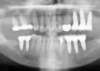

Cas 2: vues panoramiques

AVANT REHABILITATION

PENDANT REHABILITATION 3 SECTEURS MOLAIRES

APRES REHABILITATION 3 SECTEURS MOLAIRES